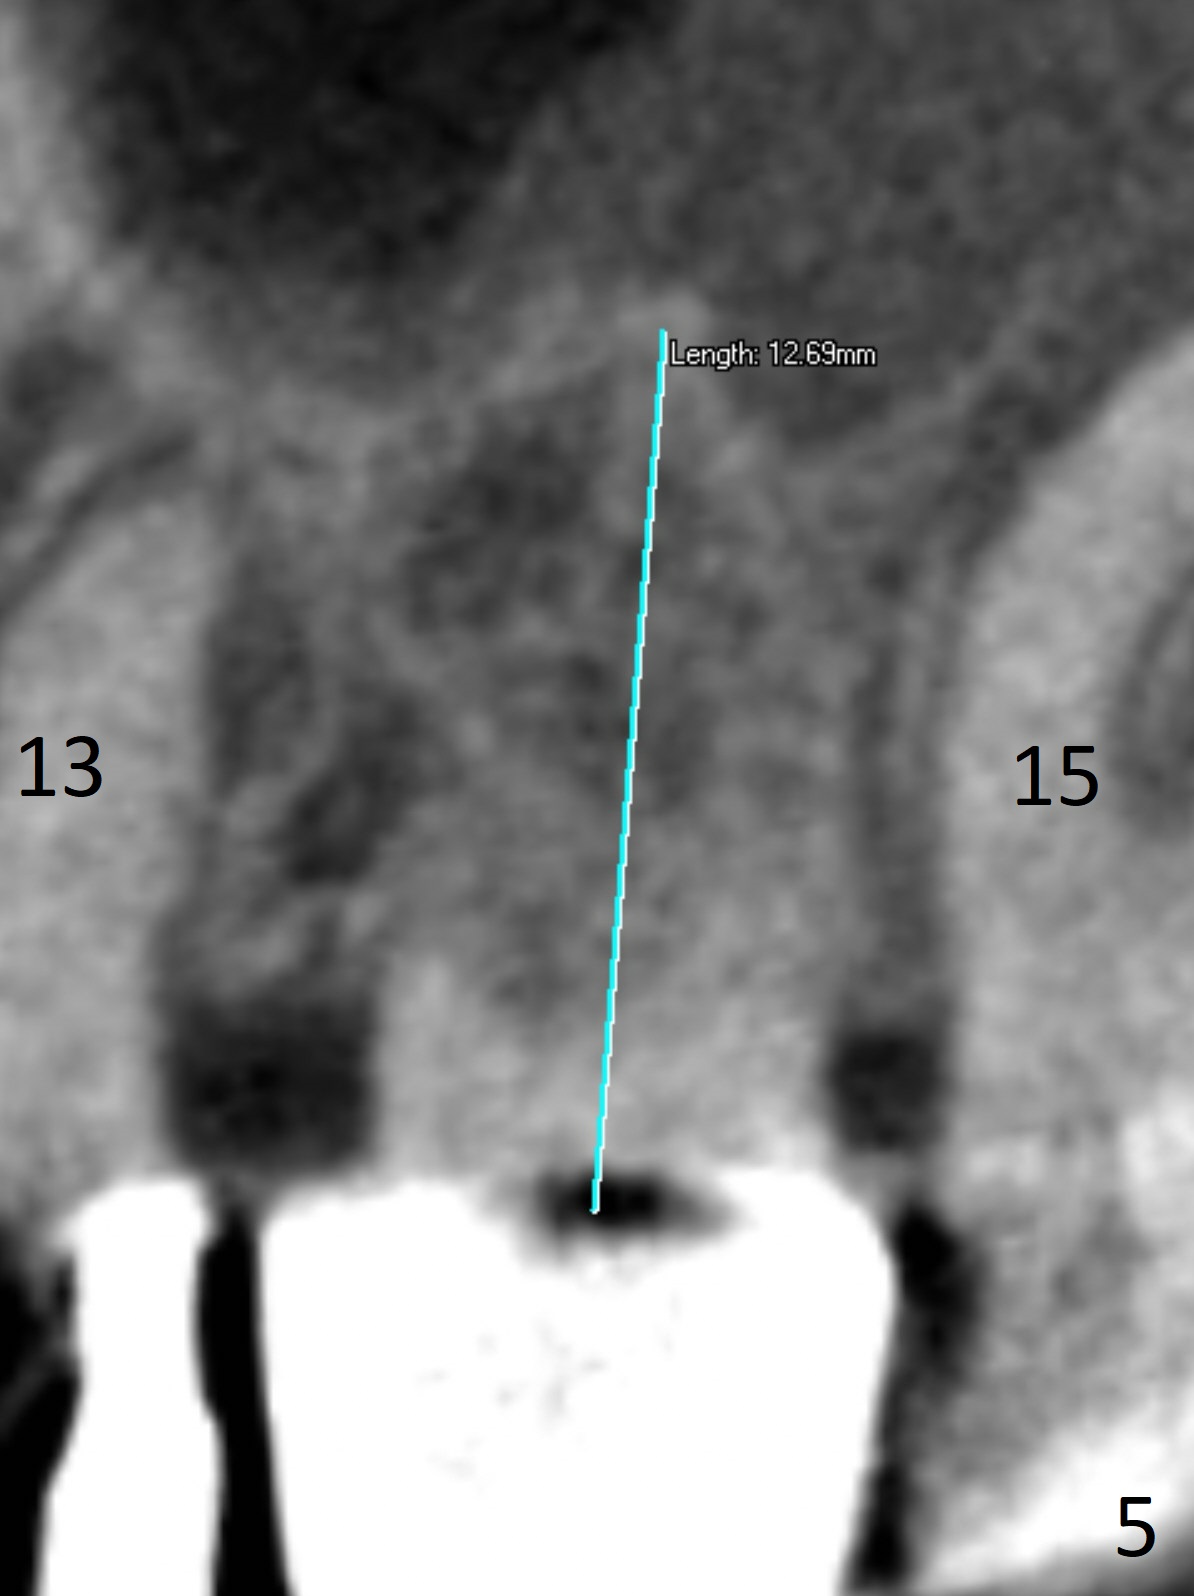

A 70-year-old woman fractures the crown at #14 (Fig.1).  A 5x11 mm implant will be placed at the septum (Fig.2).  Osteotomy depth can be determined using bony (Fig.3 with stopper) or gingival (Fig.4,5 with vision) landmark.  The CT was taken 5 years earlier.  Sagittal (Fig.6) and axial (Fig.7) sections confirm suitability of the 5x11 mm implant for the site.  Prepare surgical handpiece for sectioning the tooth for extraction.  After drills, use Magic Expanders for sinus lift.  Place Vanilla Graft prior to dummy implant(s).  A bone-level implant crown may be easier to be repaired if the proximal contact is not ideal.